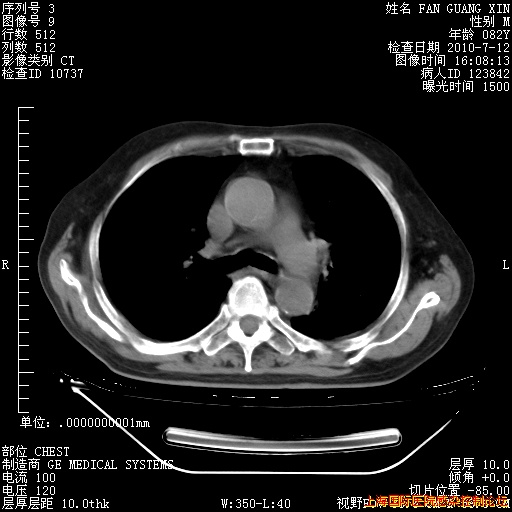

6月12日纵膈窗

整整相隔30天的肺部CT好像有所好转啊。甲强龙减量第3天,需要观察体温。